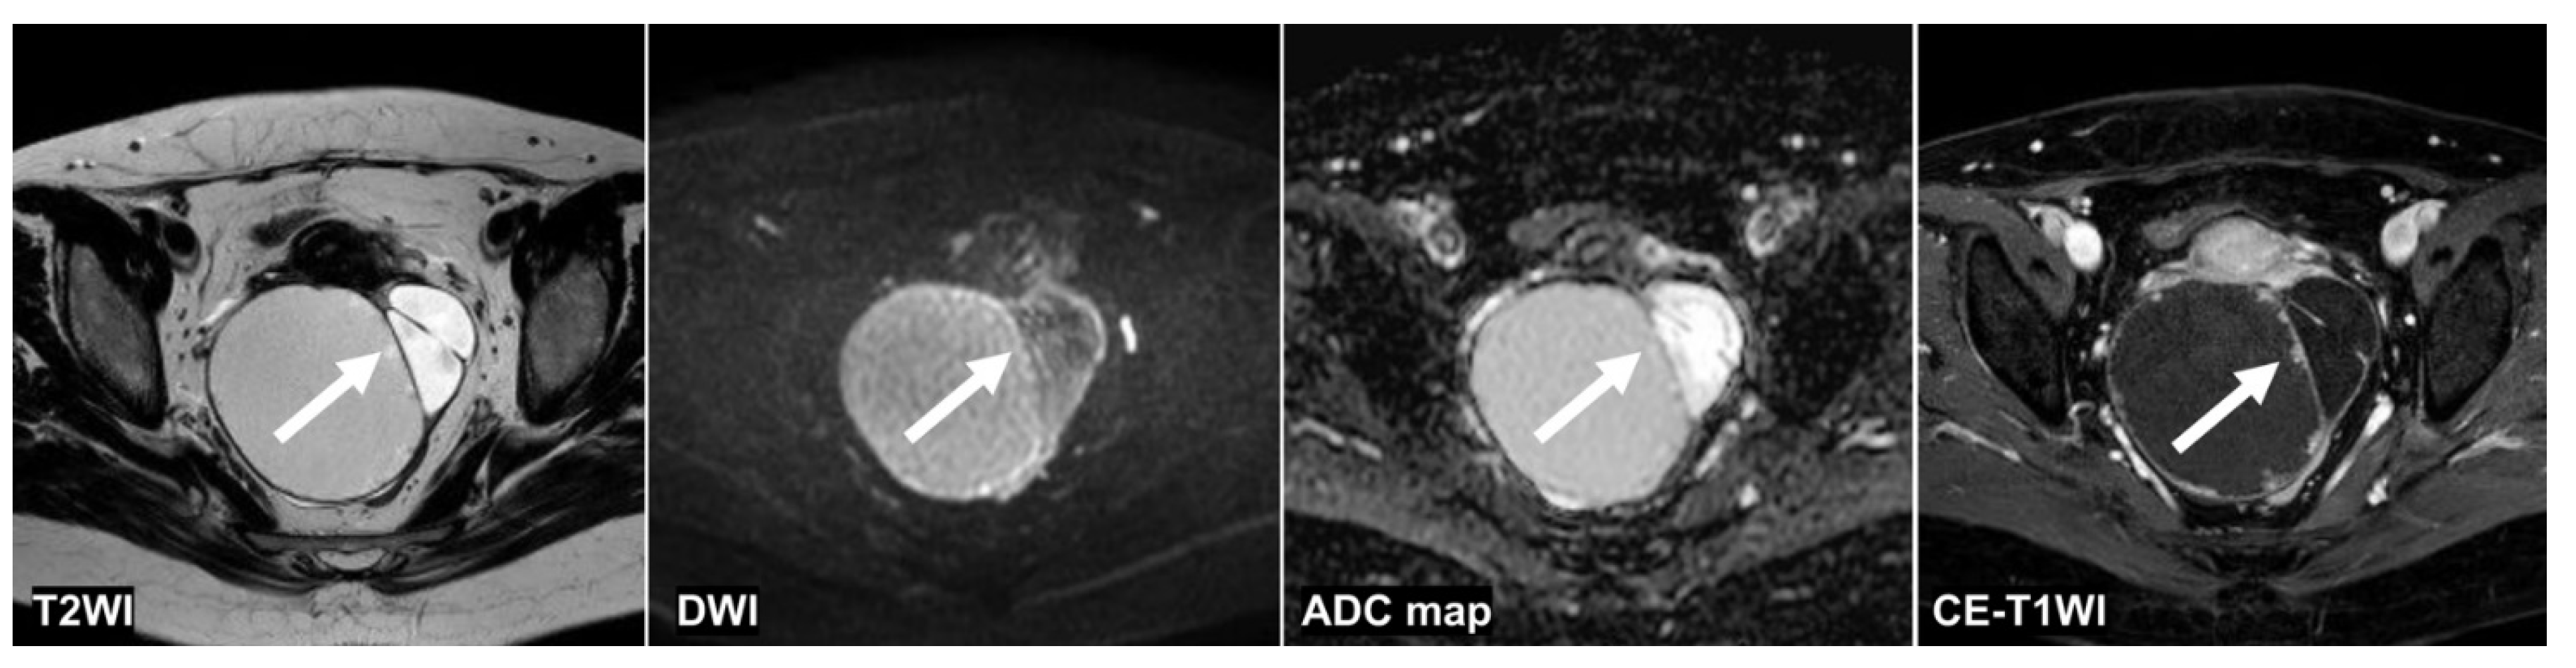

Figure 4, Figure 5 and Figure 6 show the test images of three cases in this study with different interpretations by the CNN and radiologists including the confidence value. Figure 4 and Figure 5 show the cases in which the CNN was able to make the correct diagnosis, although the radiologists had a high rate of false-negative diagnoses. Figure 4 shows a tumor with a slight signal difference between the solid components and the background on the T2WI, DWI, and ADC map. Figure 5 shows a non-malignant tumor containing components that were difficult to distinguish between solid components and mucus on the T2WI; however, the CNN diagnosed it as a non-malignant tumor. Figure 6 shows a case in which the CNN and the radiologists showed false negatives on the sequences other than the DWI, and as for the radiologists, it was assumed that the misdiagnosis was due to the difficulty in distinguishing the solid component of the ovarian tumor from the intestinal tract.

Figure 4.

A 51 year old woman with a seromucinous borderline tumor. Only the CNN could diagnose malignant tumors on the T2WI and the DWI (the CNN confidence value: malignant = 98.5% on T2WI; malignant = 99.9% on DWI). The CNN and reader 2 could diagnose malignant tumors on the ADC map (the CNN confidence value: malignant = 82.1%). On the other hand, the CNN and all radiologists could diagnose malignant tumors on the CE-T1WI (the CNN confidence value: malignant = 99.9%). This case was a typical image of seromucinous borderline or serous borderline tumor. There was almost no contrast between the papillary projections (arrow) showing hyperintensities on the T2WI and the contents of the cyst, and it was difficult to identify them, other than CE-T1WI, for the radiologists. ADC: apparent diffusion coefficient; CE-T1W1: contrast-enhanced T1-weighted imaging; CNN: convolutional neural network; DWI: diffusion-weighted imaging.